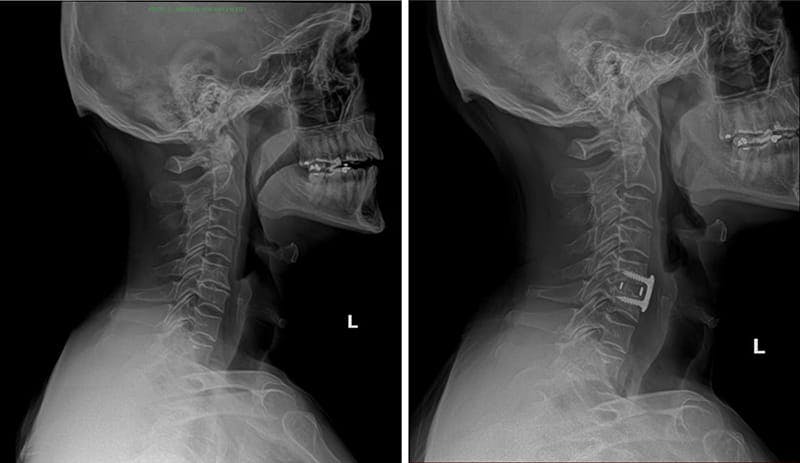

Why Might ACDF Be Recommended?

While not every neck problem requires surgery, ACDF can be a valuable option if non-surgical therapies fail or if neurological symptoms worsen. Compression of nerve roots and the spinal cord may manifest as persistent pain, numbness, or arm weakness. Indications for this procedure include:

- Degenerative disc disease in the cervical region

- Herniated discs causing arm, shoulder, or neck discomfort

- Spinal instability or progressive neurological deficits